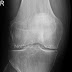

Sie denken an eine Bakercyste! Im Röntgen sehen dieses Bild:   Labor:  Leukos 12.600, CRP 260, Rotes Blutbild sonst o.B....

Das Röntgen zeigt eine unschriebene cystische Formation im lateraled Tibiaplateau. Im MRT stellt sie sich subchondral als signalreich d...

Zur Aufnahme kommt eine 70-jährige Patientin. Sie klagt über eine seit 3 Tagen bestehende Schwellung des linken Kniegelenkes. Ein Tr...